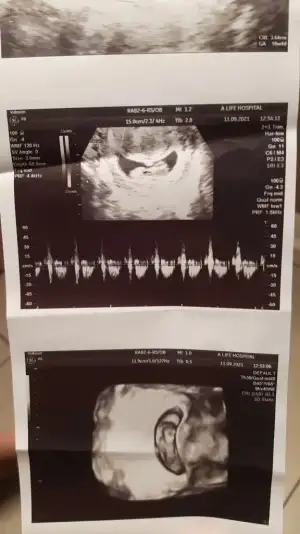

dr soylemeden siz gorun genital nub teorisi ( bebegin cinsiyeti)

Eklentiler

• IMG_20210908_223920.webp

IMG_20210908_223920.webp

25,1 KB · Görüntüleme: 120